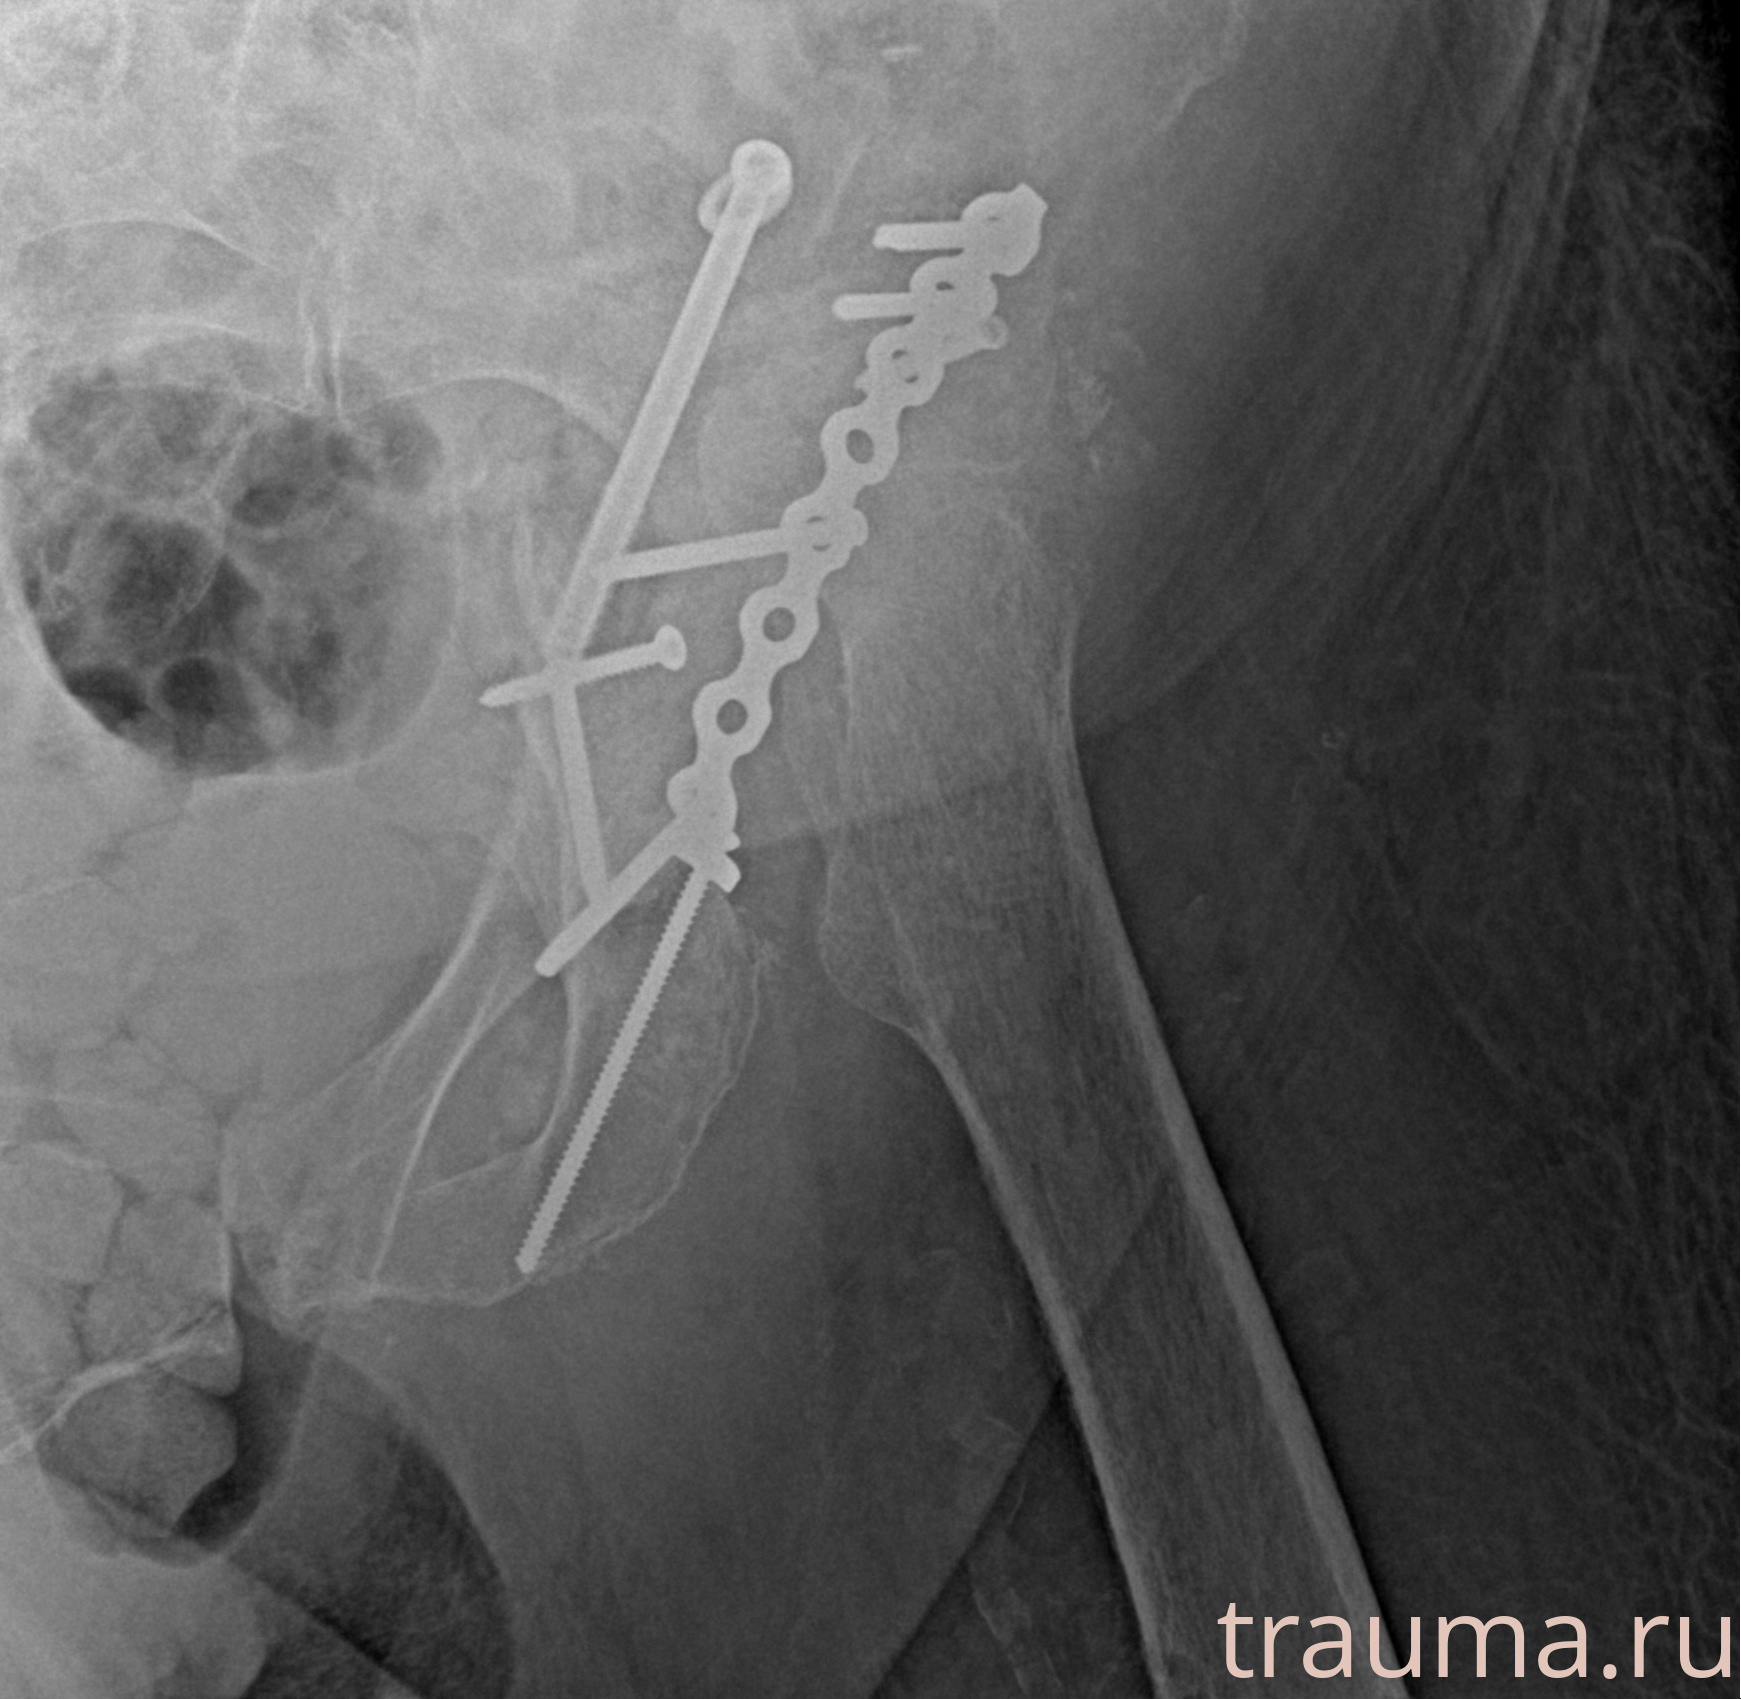

Рентгенограммы